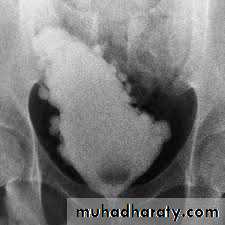

• IVU: enlarged prostate may cause round central filling defect at the bladder base and hooking of the distal ureters due to elevation of the bladder base.